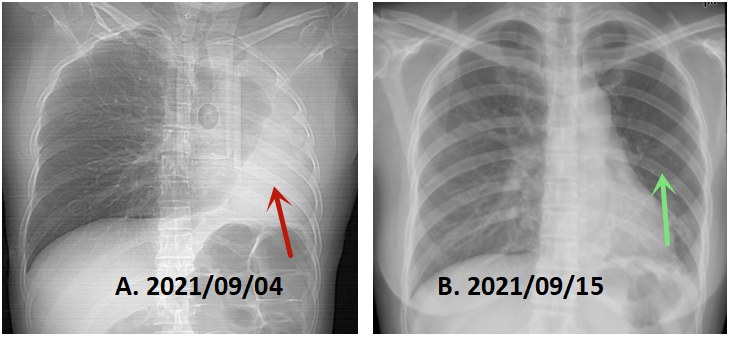

3、复查胸部X片提示左肺复张良好。(见图8)

图8 胸部X片在治疗前后的对比

A.治疗前左肺完全不张。

B.治疗后左肺大部分复张,左下肺节段性不张。